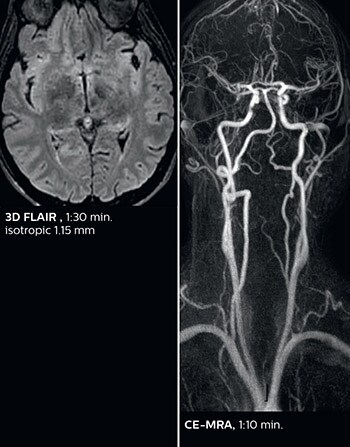

According to Dr. Savatovsky, Ingenia Elition has an impact in virtually all examinations. “We can either make the scanning faster compared to our older Ingenia 3.0T, or we save enough time so that we can add sequences we wouldn’t perform otherwise, or increase resolution. So, I think it has benefits for most of our patients.” “Some routine exams that we use every day have been shortened since we started using Elition. For example, we now use mostly a comprehensive stroke protocol (high b-value diffusion, fast 3D FLAIR, TOF, supra-aortic vessels angiography, SWIp, T1 post gad) that lasts 10 to 11 minutes, but our fast stroke protocol takes only 7 minutes. Our routine IAC needs about 10 minutes scan time and our comprehensive brain MS examination requires no longer than 13 minutes of scan time. Our ability to reduce acquisition times of most sequences helps to shorten total examination times, which in turn helps us to increase the number of patients we scan per day. “The main breakthrough for us was that Compressed SENSE and Multiband SENSE have allowed us to accelerate our examinations. Alternatively, we can invest the time gained in obtaining higher spatial resolution to see more details, or we can add additional sequences,” says Dr. Savatovsky. “That’s a big improvement from what we did before.”

The MRI center at Fondation Rothschild receives several neuro and head/neck emergency cases per day. On weekdays, an average of 7 unscheduled patients will require scanning, with approximately 4 to 5 patients actually requiring an urgent MRI scan, according to Dr. Savatovsky. He notes that the ability to accelerate sequences while maintaining image quality is particularly important in the emergency setting. “The fast scanning capabilities that came with Elition allow us to do a really quick examination and answer a lot of questions within a short time. We use every tool available to accelerate image acquisition while maintaining a reasonable image quality. So, for most of the sequences we use Compressed SENSE, for example, in our 3D FLAIR, in contrast-enhanced and noncontrast MR angiography, and for susceptibility-weighted sequences.” Among the emergencies that are routed to the MRI department at Fondation Rothschild, stroke is seen almost daily. “After arriving, acute stroke patients are immediately brought to the MRI preparation room and positioned on the FlexTrak table. There, the neurologist examines the patient and the biological workup is performed. Once this is finished, we can immediately move the patient with FlexTrak into the MRI and begin the scanning within one or two minutes. So, having the FlexTrak is a big advantage for us.”

Dr. Savatovsky appreciates the improvements and flexibility that Elition with Compressed SENSE and MultiBand SENSE provides, particularly for stroke patients. “For stroke, it allows us to cut about 5 minutes off of our stroke protocol, or to keep the same acquisition time and get more insights.” The ability to perform more sequences can help in making a swift and confident diagnosis. “For example, our stroke cases usually include the regular sequences that every center does (b1000 diffusion, FLAIR, time-of-flight angiography), but we also image supra aortic vessels, and we can replace a gradient echo sequence with a fast 50-second susceptibility-weighted sequence, and all of this doesn’t add much time. because all the regular sequences are accelerated on Elition.” “The time savings with Compressed SENSE and MultiBand SENSE make it easier to add sequences to give us additional insights. Depending on the context and the first results, we might add a DSC perfusion to assess the ischemic penumbra, an ASL perfusion to help find an alternative cause in case of normal diffusion, or add a high-resolution T1 sequence for a stroke patient, to quickly assess wall imaging in emergency cases. The additional sequences can help improve patient management, because we can already consider some alternative diagnoses if the morphological MRI is normal.”

This is an example of acute ischemic stroke with distal occlusion of the right posterior cerebral artery. Note the improved visibility of the ischemic territory on the diffusion weighted image with high b-value. The 3D FLAIR shows a distal PCA occlusion. The fast SWIp depicts the thrombus on the isolated second echo image. The total scan time (including SmartBrain, preparations and a fast 3D T1w TSE Gd) is 8:00 minutes.